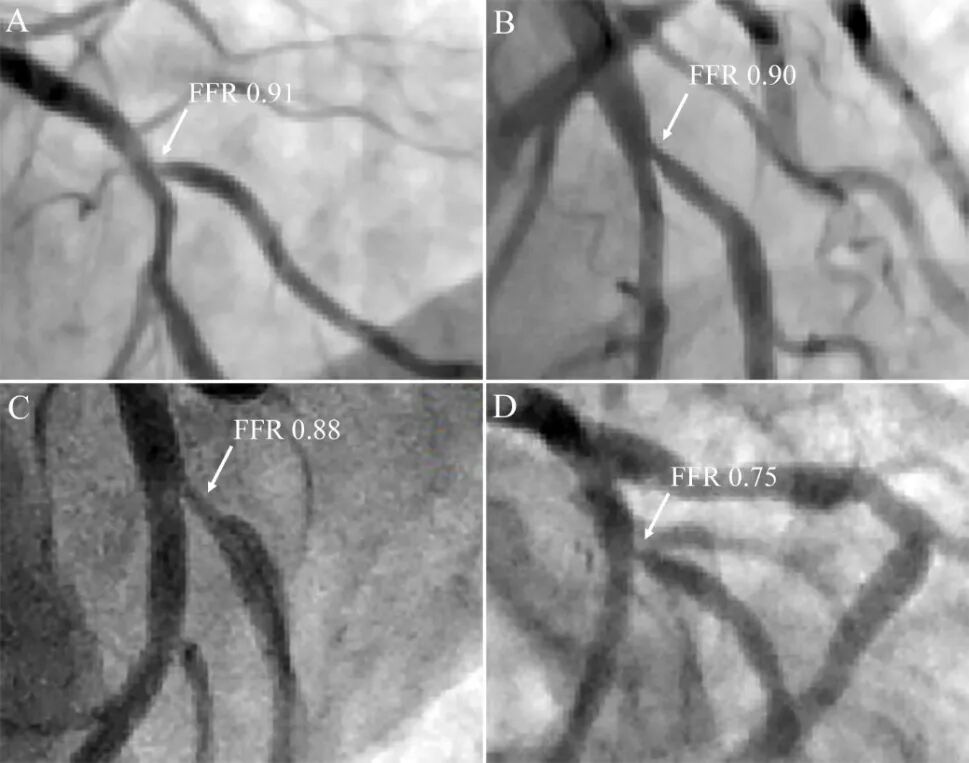

(2)缺血:缺血金标准是FFR等功能学评价,冠脉造影和腔内影像只能反映狭窄程度的解剖学改变(图2)。Koo研究[5]支架后分支开口受累情况,若造影<75% ,FFR均无意义;若造影 ≥75%,只有27%(20/73例)FFR有意义。

图2 对角支开口病变,造影容易高估狭窄程度